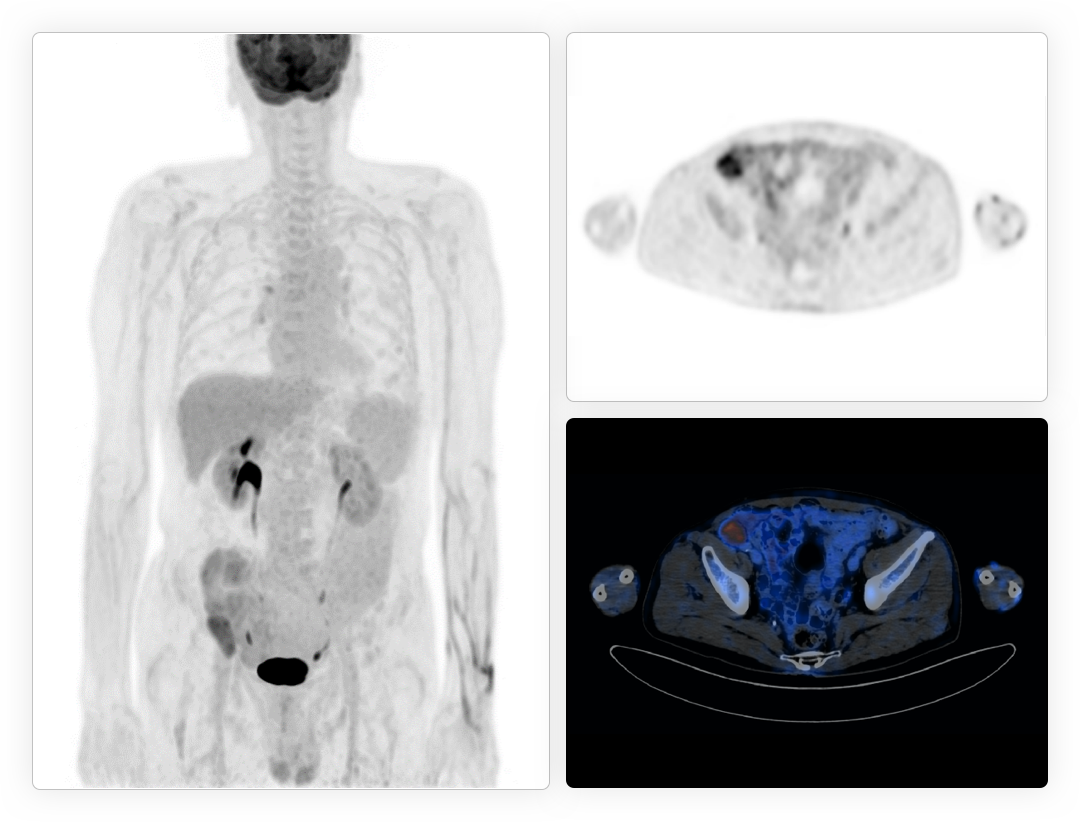

时空影像链数据源头提升CT图像质量

超高机架转速成就精准CT心脏扫描

从冠脉CTA到PET心肌灌注全套工作流

提供CT及PET全方位精准心脏功能评估*

*uWS-MI后处理工作站提供高级心分析应用